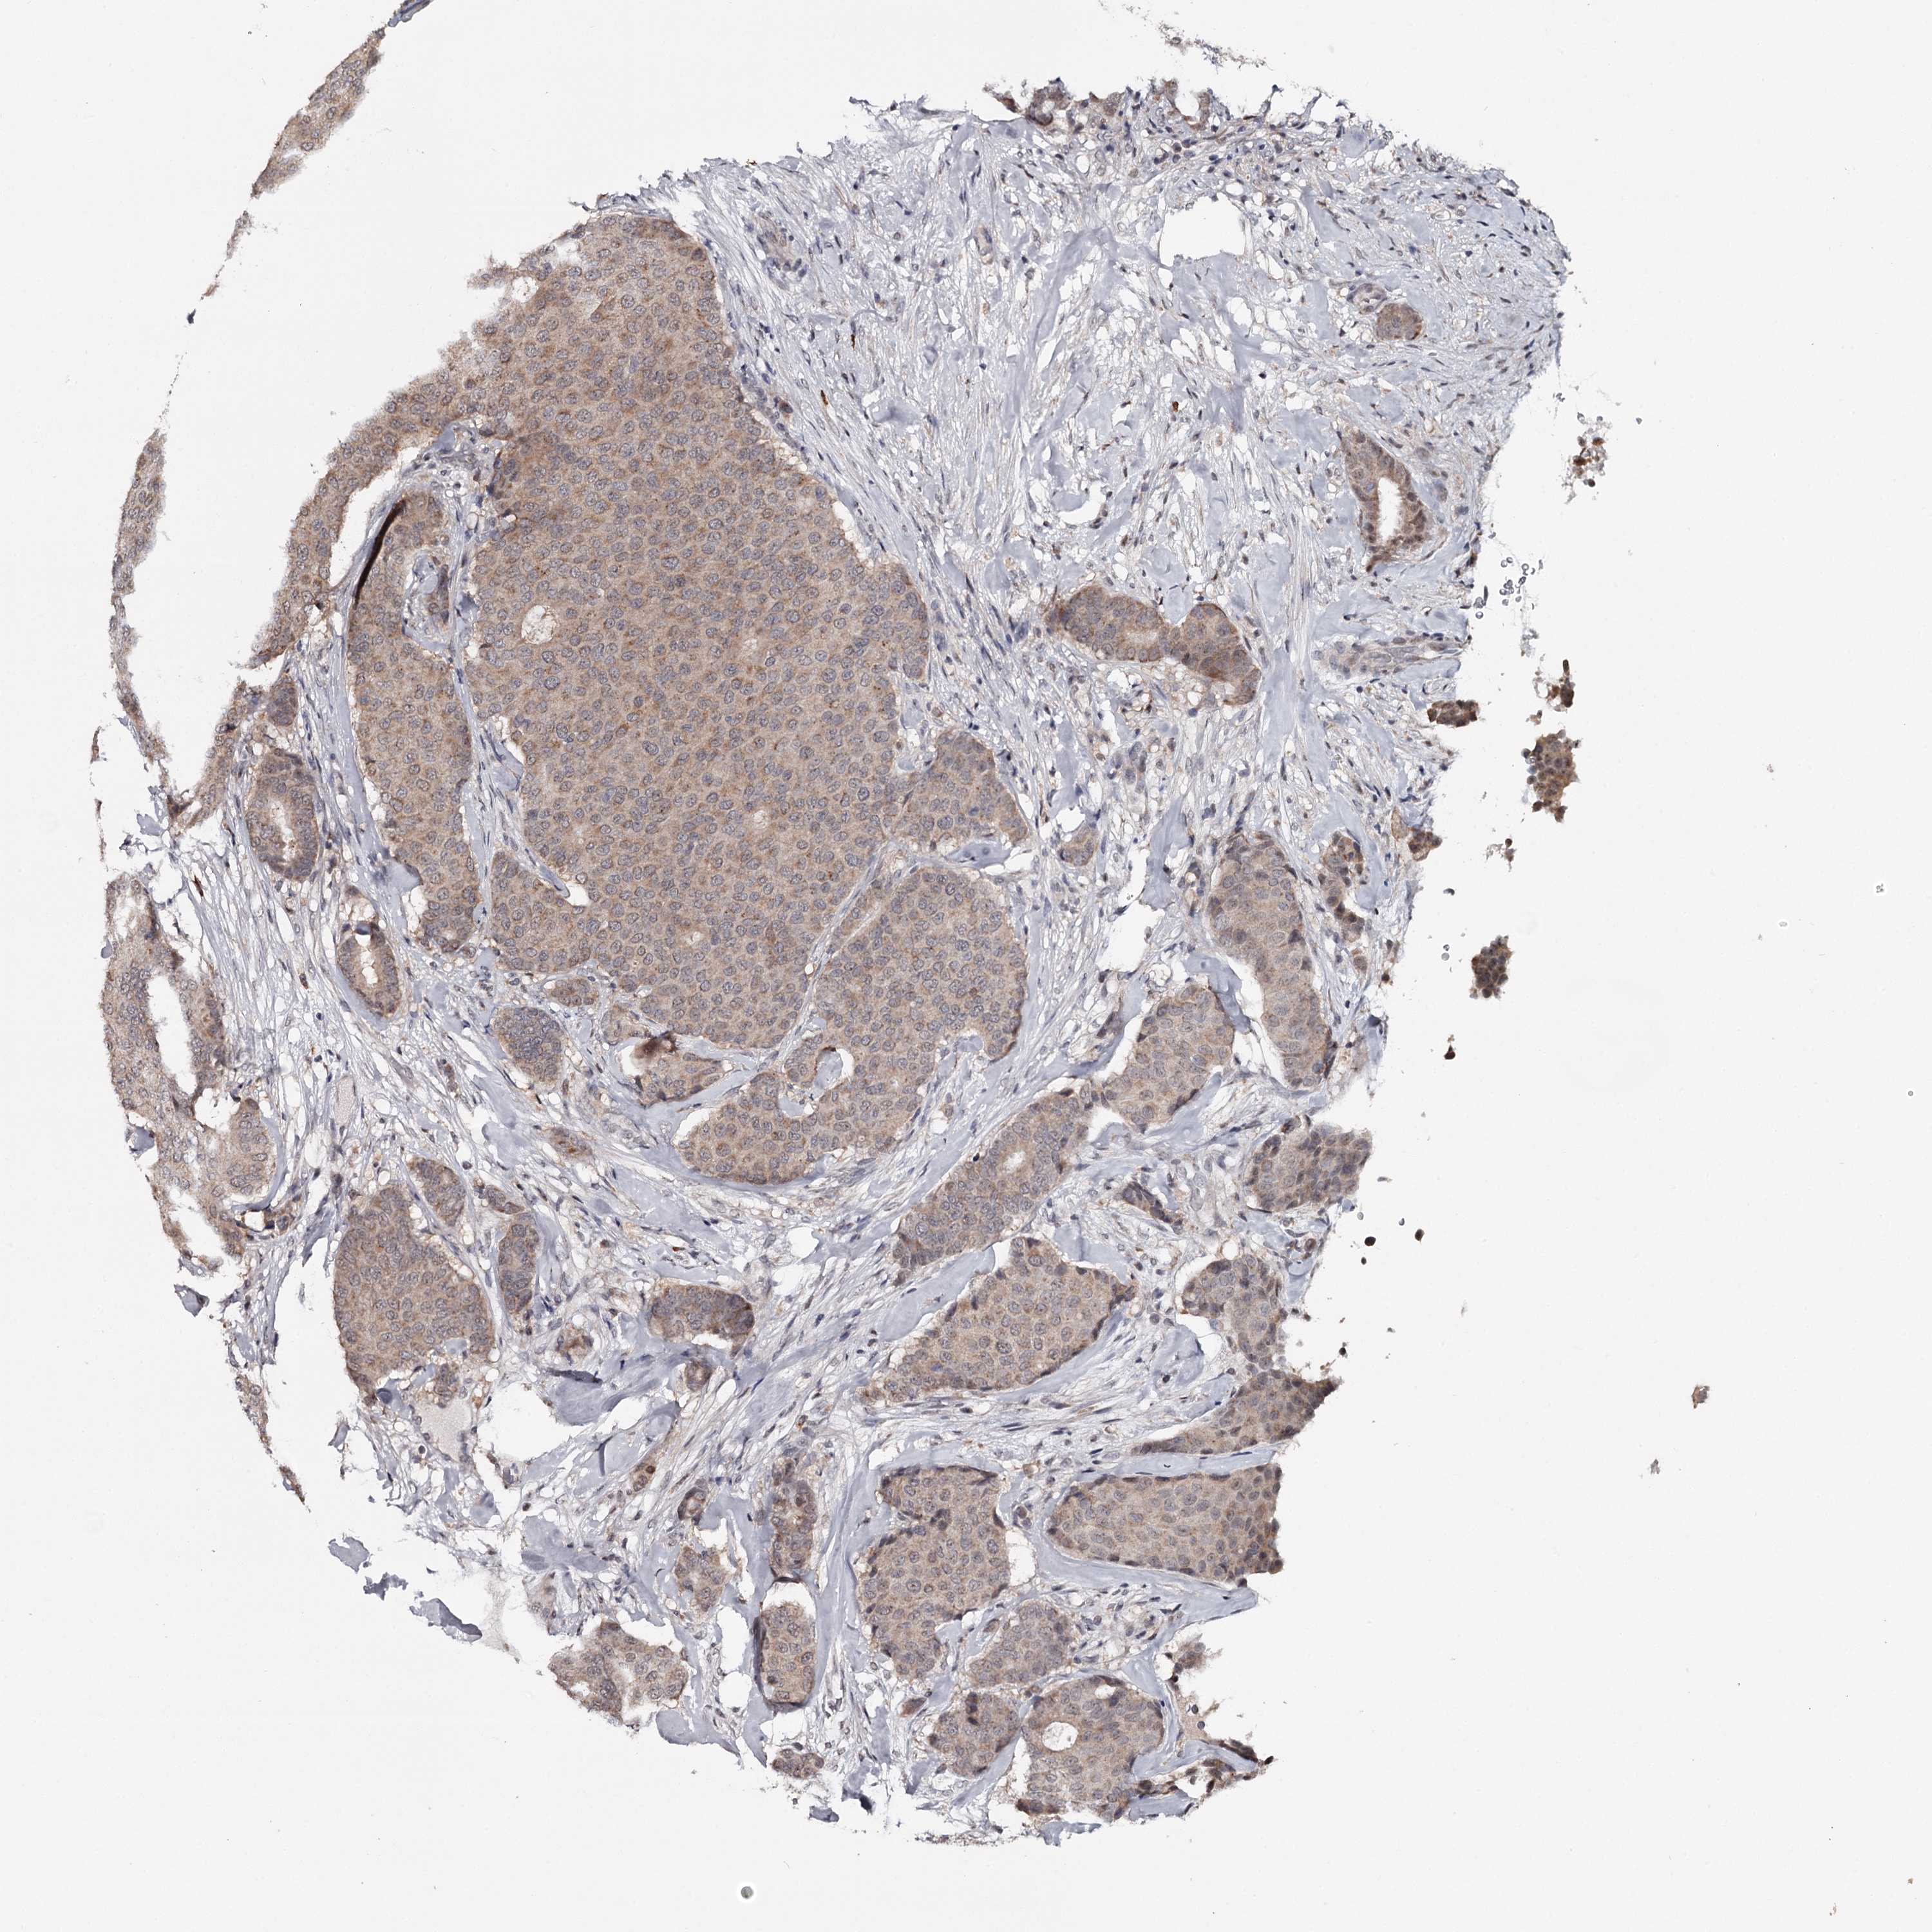

BRCA TCGA BRCA VALIDATION PROTEIN EXPRESSION